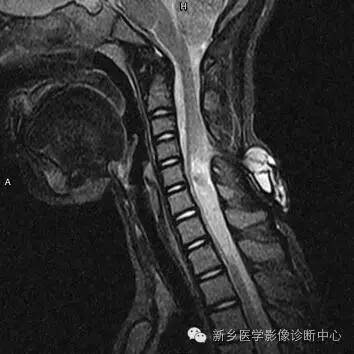

MR:

脊膜膨出:囊性肿块,与鞘膜囊想通;

脊髓脊膜膨出:囊性肿块内见脊髓或神经;

合并脊髓空洞,椎管脂肪瘤,脊髓低位,脊髓栓系,终丝粘连